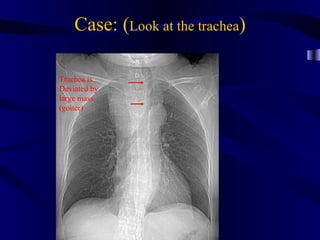

Case: (Look at the trachea)

Trachea is

Deviated by

large mass

(goiter)

Case: (Look atthe trachea) Trachea is Deviated by large mass (goiter)